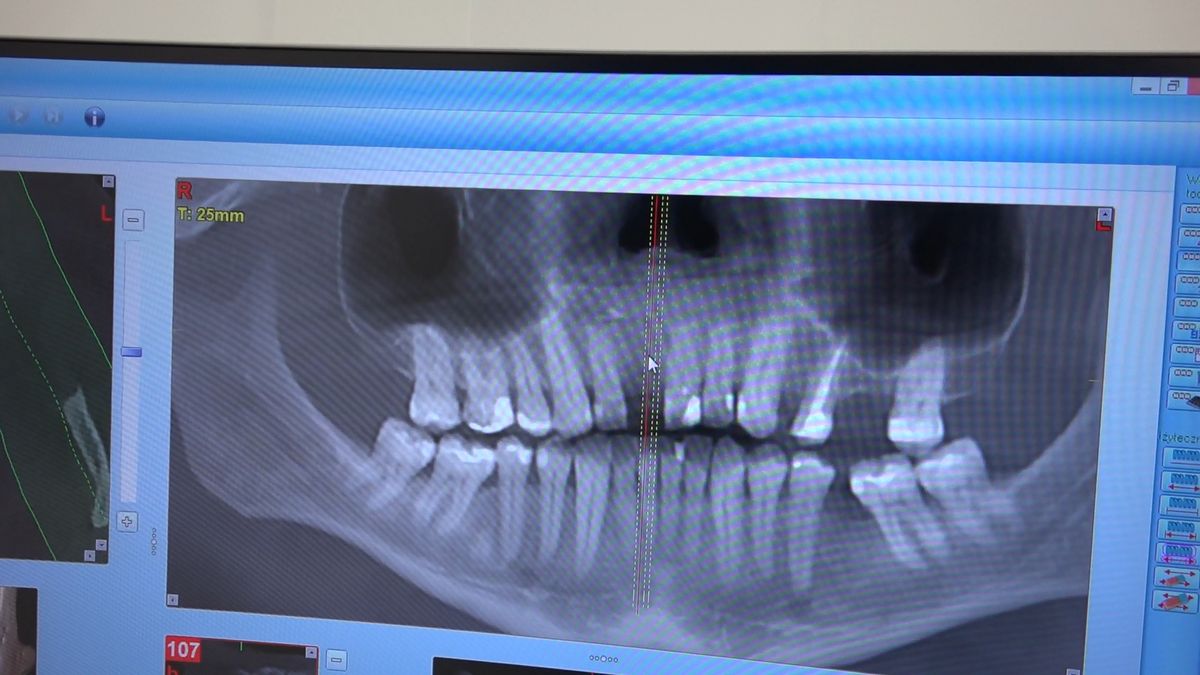

Practiculum Implantologii – Sezon VIIB, sesja 7, dzień 2